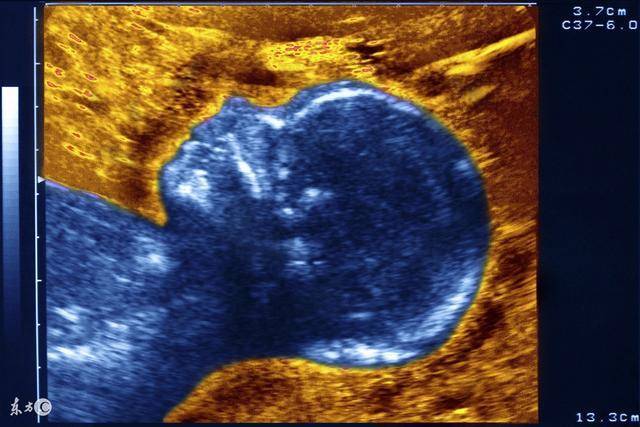

有研究表明,從妊娠5周起,胎兒就能對刺激作出反應。8周時,胎兒有蹬腳、搖頭等動作,表示開心或不愉快。儘管此時母體感受不到,但他們確實有感知了。6個月起,胎兒的情緒更積極。